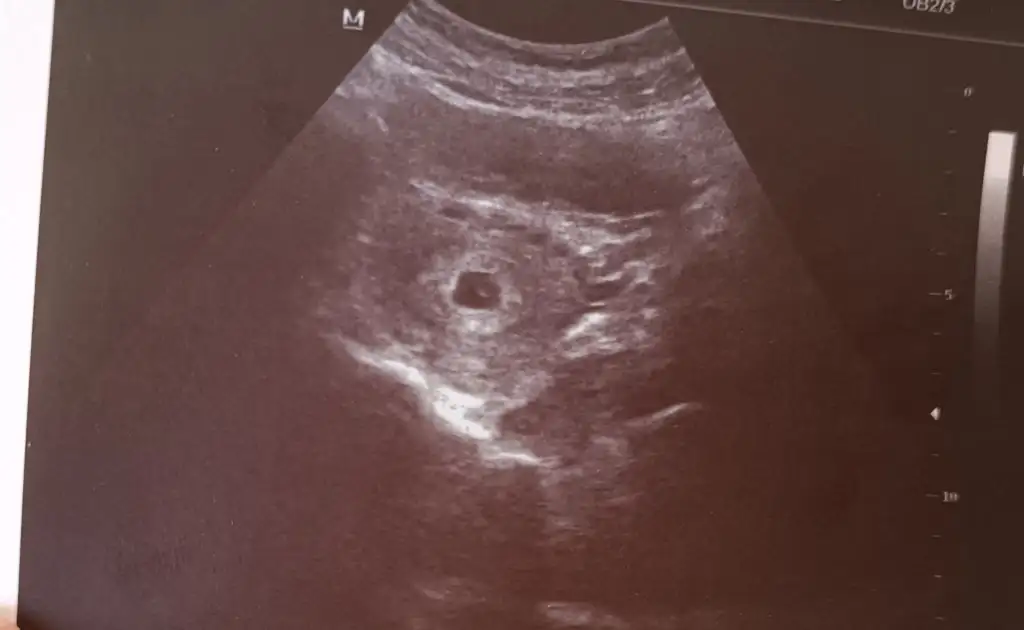

Oy maşallah çok güzelBen ve burdan 1-2 kişi daha biraz önden gidiyoruz canım ben keseyi ve yolk kesesini gördüm çok şükür kesenin içindeki beyaz minicik nokta Eki Görüntüle 3230081

Sadece keseyi gördük2 hafta sonra tekrar çagırdı